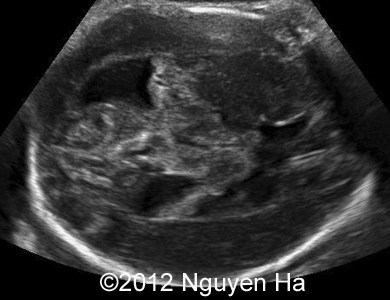

A 30-year-old woman (G1P0), with unremarkable family history, presented to our unit at 36 weeks of her pregnancy. She did not undergo any previous screening tests. Our examination (and repeated scan after four days) revealed following findings:

A 30-year-old woman (G1P0), with unremarkable family history, presented to our unit at 36 weeks of her pregnancy. She did not undergo any previous screening tests. Our examination revealed unilateral hypoechoic inhomogeneous mass within cerebral parenchyma. Our initial diagnosis was teratoma, but repeated exam after four days showed structural changes and different echogenicity of the mass and so our final diagnosis was cerebral hemorrhage. The findings were confirmed by MRI scan.

Figure 8-15: 4 days later; image 1-4 suggesting a middle cerebral artery infarction with formation of schizencephaly, no more cortex at the level of the insula.